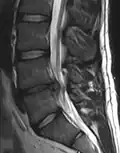

L'imagerie par résonance magnétique peut montrer la hernie, le canal vertébral, les nerfs, les tissus environnants. Les tissus mous sont les mieux analysés par cet examen qui est le plus performant pour le diagnostic de hernie discale. Les images pondérées en T2 montrent clairement la hernie.

IRM lombosacrée sagittale montrant une hernie discale de niveau L4-L5.